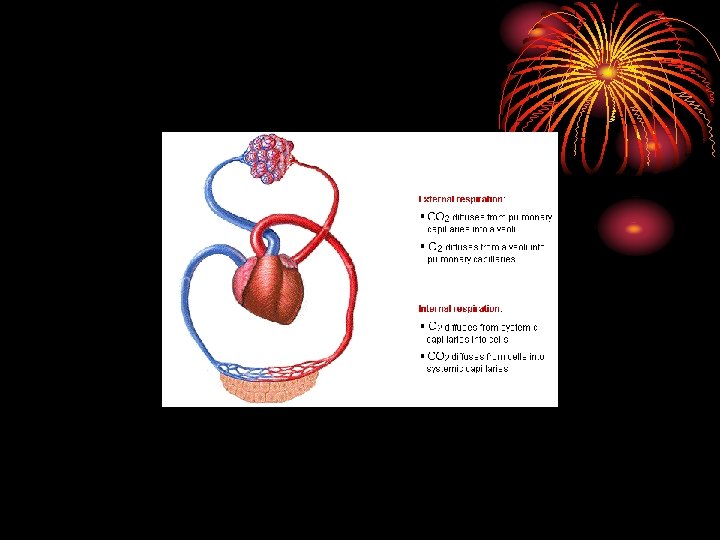

Gas transport between lungs and tissues: • Oxygen diffuses out of alveolar gas into the blood stream and CO 2 diffuses from the blood into the alveoli down their partial press. gradients. • Diffusion capacity of the lungs for a given gas is directly proportional to the alveolocapillary membrane (pulm. epithelium, capillary endothelium & their basement membranes) and inversely proportional to its thickness.